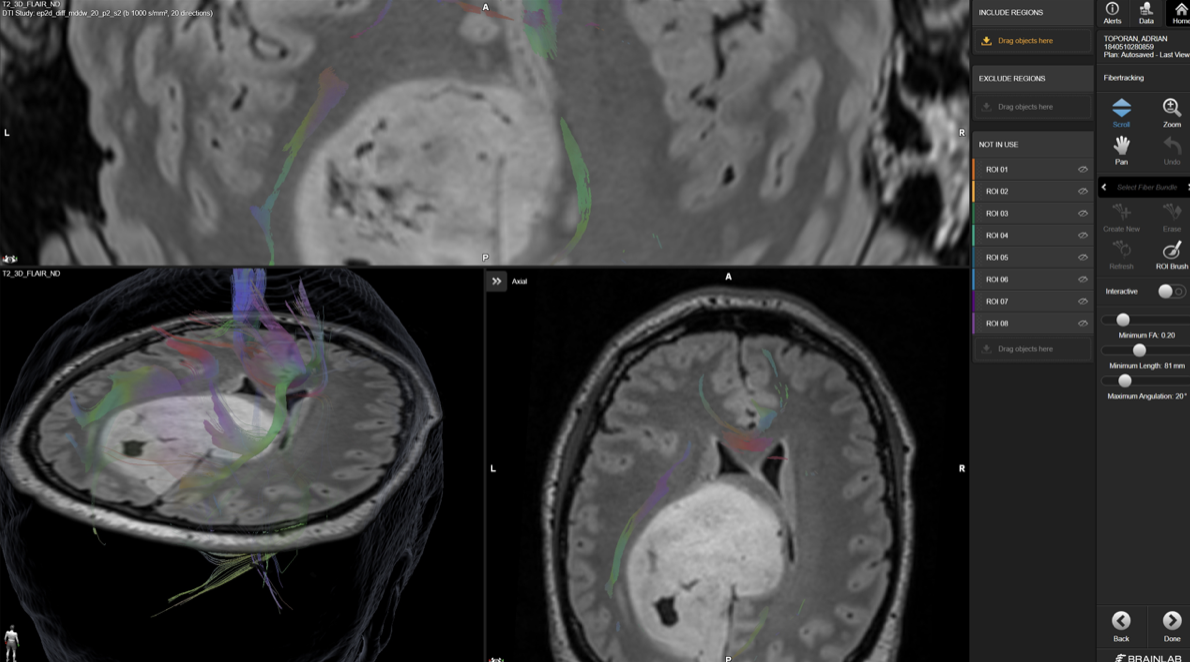

Planificare preoperatorie: cartografierea tracturilor nervoase din jurul tumorii